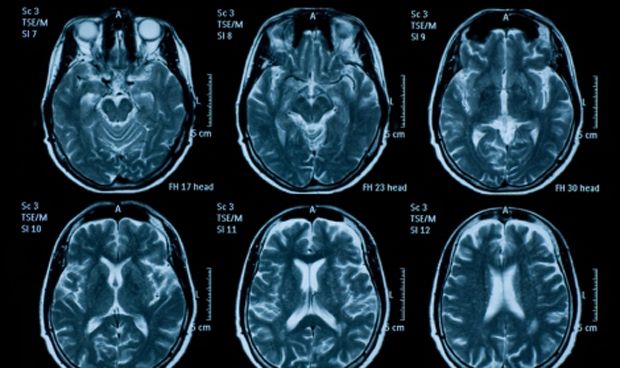

Superficie cerebelosa más plana, ligada a dificultades de comunicación

Para examinar esta región estructuralmente compleja del cerebro, los investigadores aplicaron análisis fractal 3D de alta resolución a los datos de imágenes de resonancia magnética (IRM) para estimar la dimensión fractal -una medida de la complejidad estructural- de la capa externa del cerebelo en 20 niños con autismo de 6 a 12 años y 18 controles emparejados por edad con habilidades verbales similares y volumen cerebeloso.

Así, descubrieron que los niños con autismo tenían una dimensión fractal significativamente menor, lo que indica una estructura superficial más plana, en la corteza cerebelosa derecha en comparación con los controles. Debido a que el lado derecho del cerebelo es compatible con el procesamiento del lenguaje en personas con desarrollo típico, este hallazgo sugiere que tener una superficie cerebelosa más plana puede estar relacionado con dificultades de comunicación en personas con autismo.